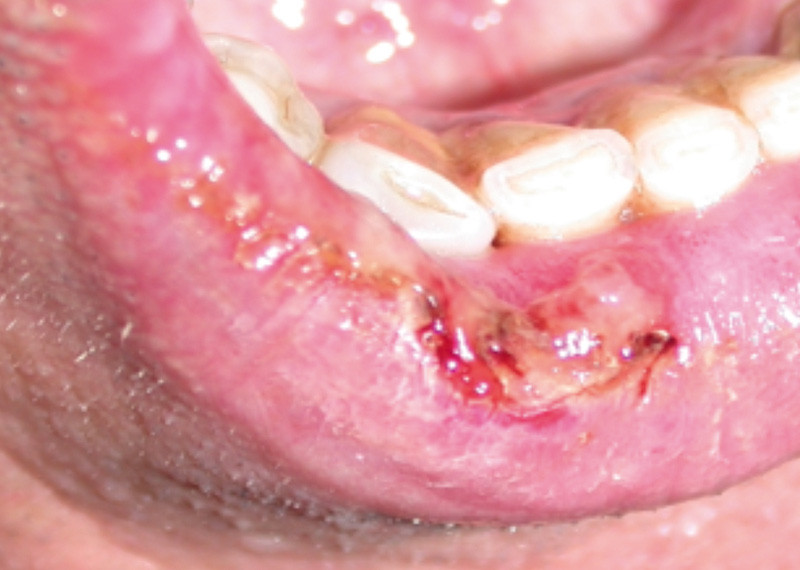

Examen clinique. Il révélait une ulcération de 2 cm de grand axe, à cheval entre la muqueuse labiale et le bord vermillon. L’ulcération était profonde, recouverte d’un enduit fibrineux humide et de quelques croûtes plus ou moins impétiginisées. L’examen intrabuccal montrait des lésions kératosiques lichénoïdes en réseau et en plaque.

Examen paraclinique. L’examen anatomopathologique d’une biopsie réalisée à cheval sur l’ulcération et la muqueuse saine révélait un infiltrat lymphoplasmocytaire lichénoïde responsable d’une pathologie d’interface pouvant correspondre à une lésion de GVH. Aucune atypie n’était décelée sur le prélèvement.

Synthèse. Le tableau clinique et l’examen anatomopathologique étaient évocateurs d’une lésion lichénoïde de GVH. Dans le contexte, le diagnostic de lésion lichénoïde de GVH était évident, mais une biopsie était nécessaire pour éliminer une dégénérescence en carcinome épidermoïde. Le traitement…